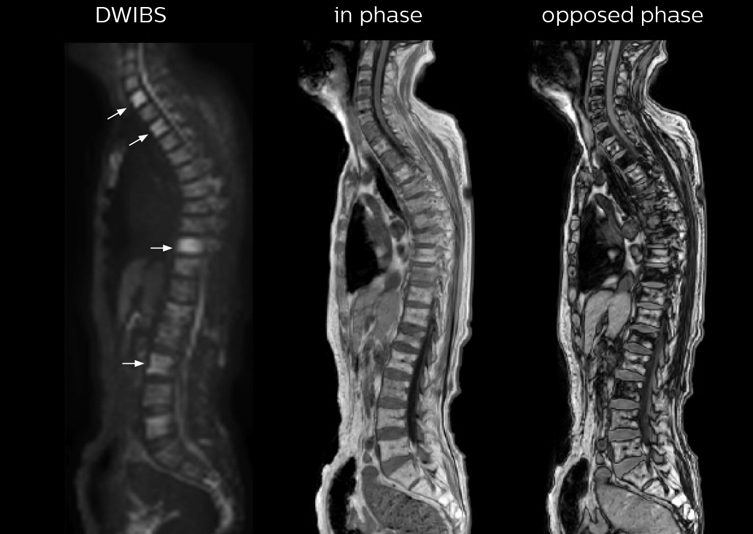

The single shot T2-weighted TSE images are used for morphology and compared to DWIBS images to identify T2 shine-through. Sagittal STIR images are used in patients with inflammation or bone metastasis.

“In-phase and out-phase sagittal T1-weighted FFE images help us to visualize and further characterize bone lesions such as metastasis and bone-marrow hyperplasia that have high signal on DWI. These images are also used throughout radiotherapy, to monitor changes in the fatty bone marrow.”